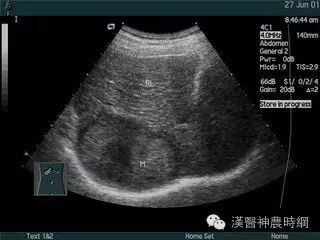

1.超声检查  B超检查用于肝癌诊断具有无损伤、无放射损害、简便、价廉、敏感度高、可重复性等优点。它可显示肿瘤的大小、形状、部位、肿瘤与血管的关系以及肝静脉、门静脉有无癌栓等,其诊断符合率可达90%。B超可检出1~2cm的小肝癌,最小直径为0.5~0.7cm。文献报道高分辨力B超对0.5~2.0cm的肝内微小灶的发现率较高,但定性诊断的准确率仅为58%。

近年国内外均有人采用超声对比剂,如铁或钆等行声学造影,有助于定性诊断和确定病灶大小。原发性肝癌B超图像常显示肝体积增大,病变向肝表面隆起,周围常有声晕等。其回声可表现为低回声型、高回声型和混合回声型。小肝癌常呈低回声型,大肝癌或呈高回声,或高低回声混合,并可见中心坏死液化的无回声区。B超检查可因肺、胃等器官遮盖存在盲区,造成遗漏病变,如右膈下、左外叶上段等。微小病变位于肝实质深部并伴有严重肝硬化时,常难以辨认。另外与操作者的经验和检查是否细致均有关。